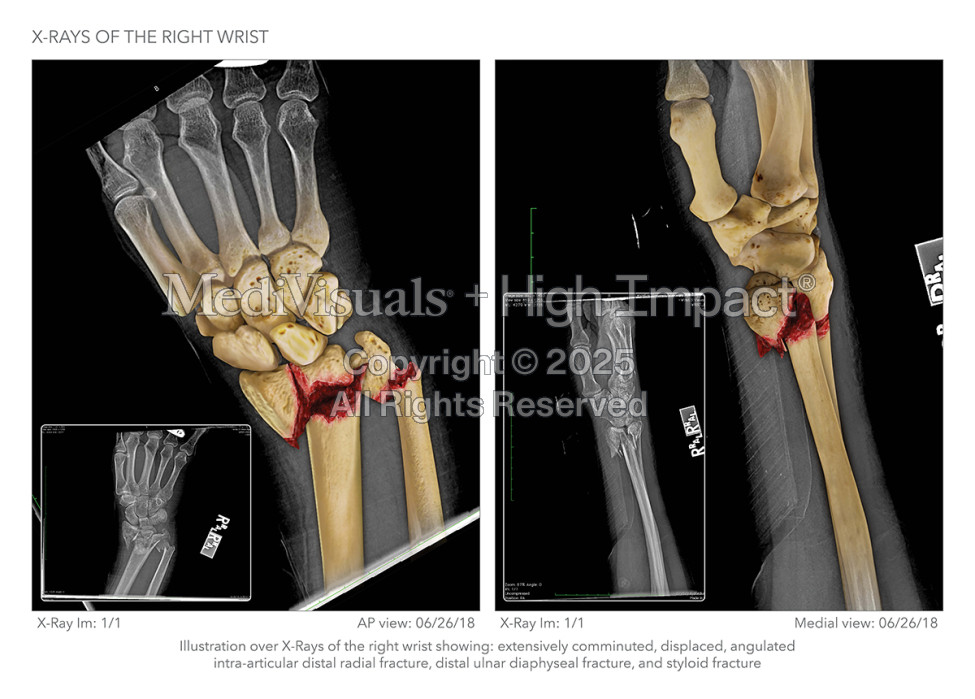

Mr. Sandefur needed the three Defendant contractors to understand the level of damage his client suffered as a result of their poorly conceived floor design that failed to comply with building standards. He tasked our medical illustration team with building an illustration series that would break down his client’s injuries, starting with the wrist.